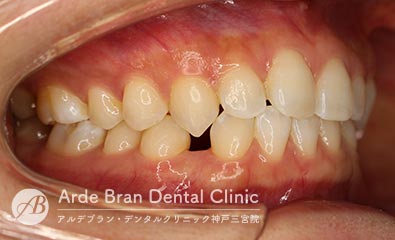

- 叢生/八重歯/歯のがたつき(20代女性 治療期間2年)

- 上下の犬歯の突出と歯のがたつきを主訴に来院されました。特に上下ともに犬歯が大きく前に出ており、噛み合わせに悪影響を及ぼしている状態でした。歯列のスペース不足が顕著であったため、上下左右の第一小臼歯を4本抜歯し、適切な歯列を確保する方針としました。治療では、上下の犬歯を正しい位置へ誘導しながら、全体の噛み合わせを調整。歯列のアーチを整え、前歯のねじれやガタつきも改善しました。治療後は、上下の犬歯が適切な位置に収まり、口元のラインがすっきりと改善。歯並びだけでなく、噛み合わせや清掃性の向上にもつながり、機能的で美しい口元を実現しました。

- 治療前

- 治療後

| 装置名 | インビザライン(マウスピース矯正) |

| 抜歯非抜歯 | 4本抜歯 |

| 治療期間 | 2年 |

| 費用 | インビザラインフル72万円+TAX |

| リスク副作用 | 装置装着による違和感、歯の移動時の痛み、歯根吸収など。詳しくはこちらをご参照ください。 |